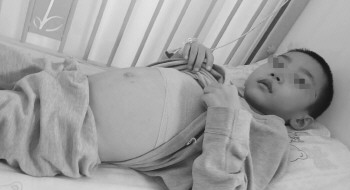

小宇肚子鼓胀,腹内肿瘤巨大。

董兴举没有多想,可撩起儿子的衣服一看,心里咯噔一下。董兴举发现儿子的肚子鼓胀得不正常,并不是吃撑了的那种鼓,摁起来发硬,敲起来声音也不对。孩子这样多长时间了?奶奶也回答不上不来,儿子平时饭量少,身体很瘦,肚子本来就显得大一些,而且是整体圆鼓鼓的,并没有局部鼓胀的现象,再加上冬天衣服比较厚实,肚子大的问题从来没有人注意过。而且,儿子也从来没有跟大人说起身体有什么疼痛等不适。

现在孩子的肿瘤长在腹膜后面,肝脏也弥漫性肿大,因为肿瘤的体积太大无法手术,目前需要先化疗,“看着孩子在病床上难受的样子,我宁愿去替他承受这份痛苦。”董兴举说。